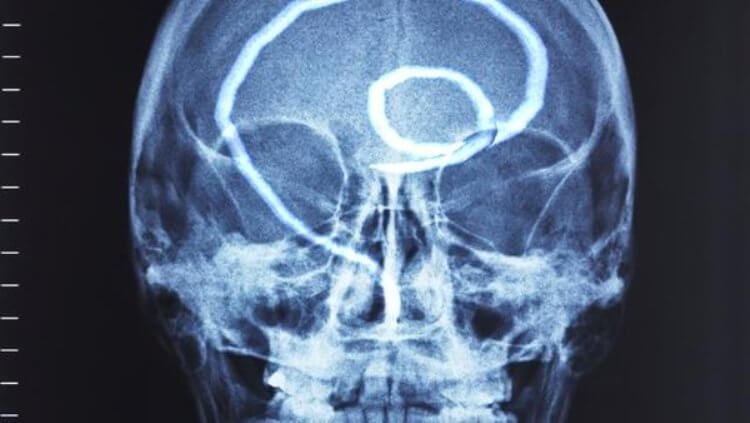

Paraziti u ljudskom mozgu mogu da izazovu rak:

Još jedan čest slučaj je zaraza ljudskog mozga. Ovde dolazi do poremećaja funkcija, nervoze, umora, preterane razdražljivosti i iznenadnih promena raspoloženja. U kasnijoj fazi, kako se mozak puni parazitima, razvijaju se neke ozbiljnije bolesti i na kraju nastupa smrt.

"Imamo foto arhivu: fotografije snimljene za vreme autopsije kada smo otkrili različite parazite u ljudskim organima. Evo nekoliko primera. Upozoravam vas, užasni su".